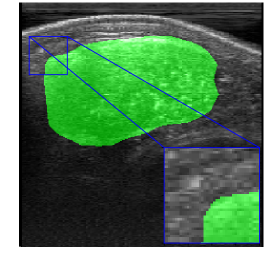

Rib Eye Area (REA). This image dataset consists of ultrasound images of the Longissimus dorsi muscle between the 11th and 13th ribs of cattle. The goal is to automatically calculate the rib eye area (REA), an important region for decision making during cattle breeding. The main challenge is the uncertainty in the REA annotation, since the image is noisy and even experts have difficulty in delimiting the borders of this region. Fig. 3 presents examples of images and the annotation made by a specialist. We can observe that some borders are absent and depend on the subjectivity and knowledge of the annotator. To evaluate the segmentation methods, 76 images with 309×213309213309\times 213 resolution were obtained and labeled by an expert. Due to the number of images, the division of the images in training and testing followed 5-fold cross-validation.

Refer to caption

Figure 3: Sample images from Rib Eye Area (REA) dataset.

REA dataset. This image dataset has high uncertainty during labeling due to noise from the ultrasound image. In some cases, the border of REA is not completely visible and must be estimated by the specialist. Therefore, the proposed approach becomes essential to obtain accurate segmentation at the edges. The segmentation examples in Fig. 6 show that the baseline was not able to define the REA correctly due to the uncertainty of the labeling. On the other hand, the proposed approach presents results close to the specialist in regions that the border needs to be estimated.